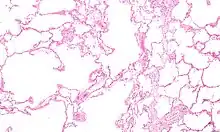

.jpg.webp) | |

| Section of a lung showing centrilobular emphysema, with enlarged airspaces in the centre of a lobule usually caused by smoking and a major feature of COPD | |

Chronic obstructive pulmonary disease (COPD) is a type of progressive lung disease characterized by long-term respiratory symptoms and airflow limitation.[8] The main symptoms of COPD include shortness of breath and a cough, which may or may not produce mucus.[4] COPD progressively worsens, with everyday activities such as walking or dressing becoming difficult.[3] While COPD is incurable, it is preventable and treatable. The two most common types of COPD are emphysema and chronic bronchitis and have been the two classic COPD phenotypes. However, this basic dogma has been challenged as varying degrees of co-existing emphysema, chronic bronchitis, and potentially significant vascular diseases have all been acknowledged in those with COPD, giving rise to the classification of other phenotypes or subtypes.[9] Emphysema is defined as enlarged airspaces (alveoli) whose walls have broken down resulting in permanent damage to the lung tissue. Chronic bronchitis is defined as a productive cough that is present for at least three months each year for two years. Both of these conditions can exist without airflow limitation when they are not classed as COPD. Emphysema is just one of the structural abnormalities that can limit airflow and can exist without airflow limitation in a significant number of people.[10][11] Chronic bronchitis does not always result in airflow limitation but in young adults with chronic bronchitis who smoke, the risk of developing COPD is high.[12] Many definitions of COPD in the past included emphysema and chronic bronchitis, but these have never been included in GOLD report definitions.[8] Emphysema and chronic bronchitis remain the predominant phenotypes of COPD but there is often overlap between them and a number of other phenotypes have also been described.[9][13] COPD and asthma may coexist and converge in some individuals.[14] COPD is associated with low-grade systemic inflammation.[15]

Definition

COPD develops as a significant and chronic inflammatory response to inhaled irritants which ultimately leads to bronchial and alveolar remodelling in the lung known as small airways disease.[93][94] Thus, airway remodelling with narrowing of peripheral airway and emphysema are responsible for the alteration of lung function.[55] Mucociliary clearance is particularly altered with a dysregulation of cilia and mucus production.[95] Small airway disease sometimes called chronic bronchiolitis, appears to be the precursor for the development of emphysema.[96] The inflammatory cells involved include neutrophils and macrophages, two types of white blood cells. Those who smoke additionally have cytotoxic T cell involvement and some people with COPD have eosinophil involvement similar to that in asthma. Part of this cell response is brought on by inflammatory mediators such as chemotactic factors. Other processes involved with lung damage include oxidative stress produced by high concentrations of free radicals in tobacco smoke and released by inflammatory cells and breakdown of the connective tissue of the lungs by proteases (particularly elastase) that are insufficiently inhibited by protease inhibitors. The destruction of the connective tissue of the lungs leads to emphysema, which then contributes to the poor airflow and finally, poor absorption and release of respiratory gases. General muscle wasting that often occurs in COPD may be partly due to inflammatory mediators released by the lungs into the blood.[12]